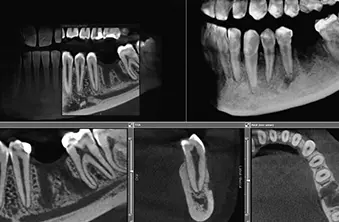

Sodobna rentgenska diagnostika, ki je na voljo pri nas, obsega:

Dobro znamo poskrbeti za zdrave in lepe nasmehe. Terapije, zobni rentgen in vse ostalo izvajamo z najsodobnejšo diagnostično opremo, vrhunskimi materiali in pripomočki. Pri tem nam seveda ne manjka znanj in prakse, kar stalno bogatimo, da pri nas resnično dobite zobozdravstveno oskrbo na najvišjem možnem nivoju.